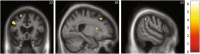

Results: Dysphagia was significantly more prevalent in nfvPPA (43% vs. 5% svPPA and no lvPPA). The machine learning model revealed a hierarchy of features predicting dysphagia in the nfvPPA group, with excellent classification accuracy (90.5%, 95% confidence interval = 77.9-100); the strongest predictor was orofacial apraxia, followed by older age, parkinsonism, more severe behavioural disturbance, and more severe cognitive impairment. Significant grey matter atrophy correlates of dysphagia in nfvPPA were identified in left middle frontal, right superior frontal, and right supramarginal gyri and right caudate.